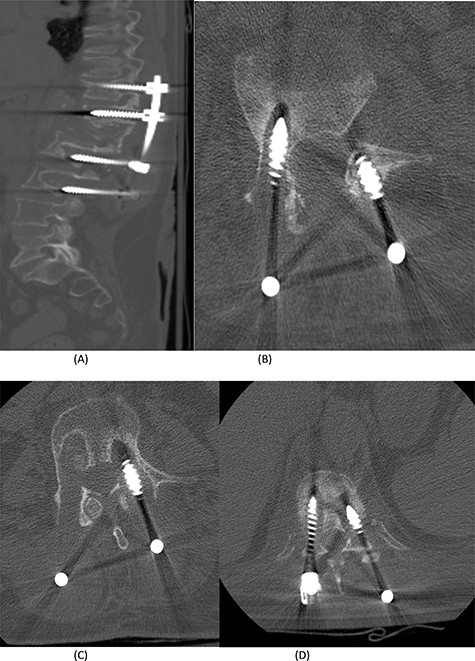

(A) Sagittal spine CT demonstrating a burst fracture involving L1 vertebral body with retropulsion of fragments and epidural soft tissue mass indenting the conus medullaris at the level of T12–L1. (B) Axial spine CT of the corresponding level of L2 vertebral body. (C) Axial spine CT of the corresponding level of L3 vertebral body. (D) Axial spine CT of the corresponding level of T11 vertebral body.

(A) Sagittal spine CT demonstrating healed bone and re-ossification of T11-L3. (B) Axial spine CT of the corresponding level of T11 vertebral body.